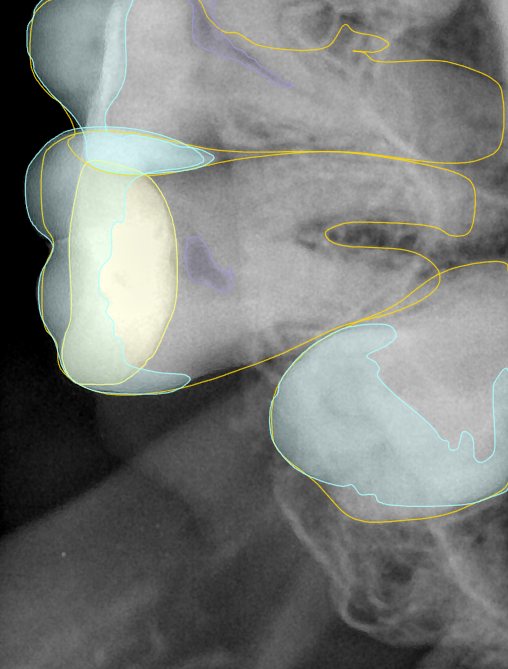

CR/DR 牙齿分割阶段记录

当前进展

- 完成了 CR/DR 牙齿相关分割训练

- 当前结果已经达到阶段预期,但仍有细节问题需要继续处理

相关测试

遇到的问题

- 训练过程中出现过 mask 下移问题

- 部分结果会出现 box 填充异常

- mask 边缘仍然有比较明显的锯齿感

参考

第二版算法问题测试